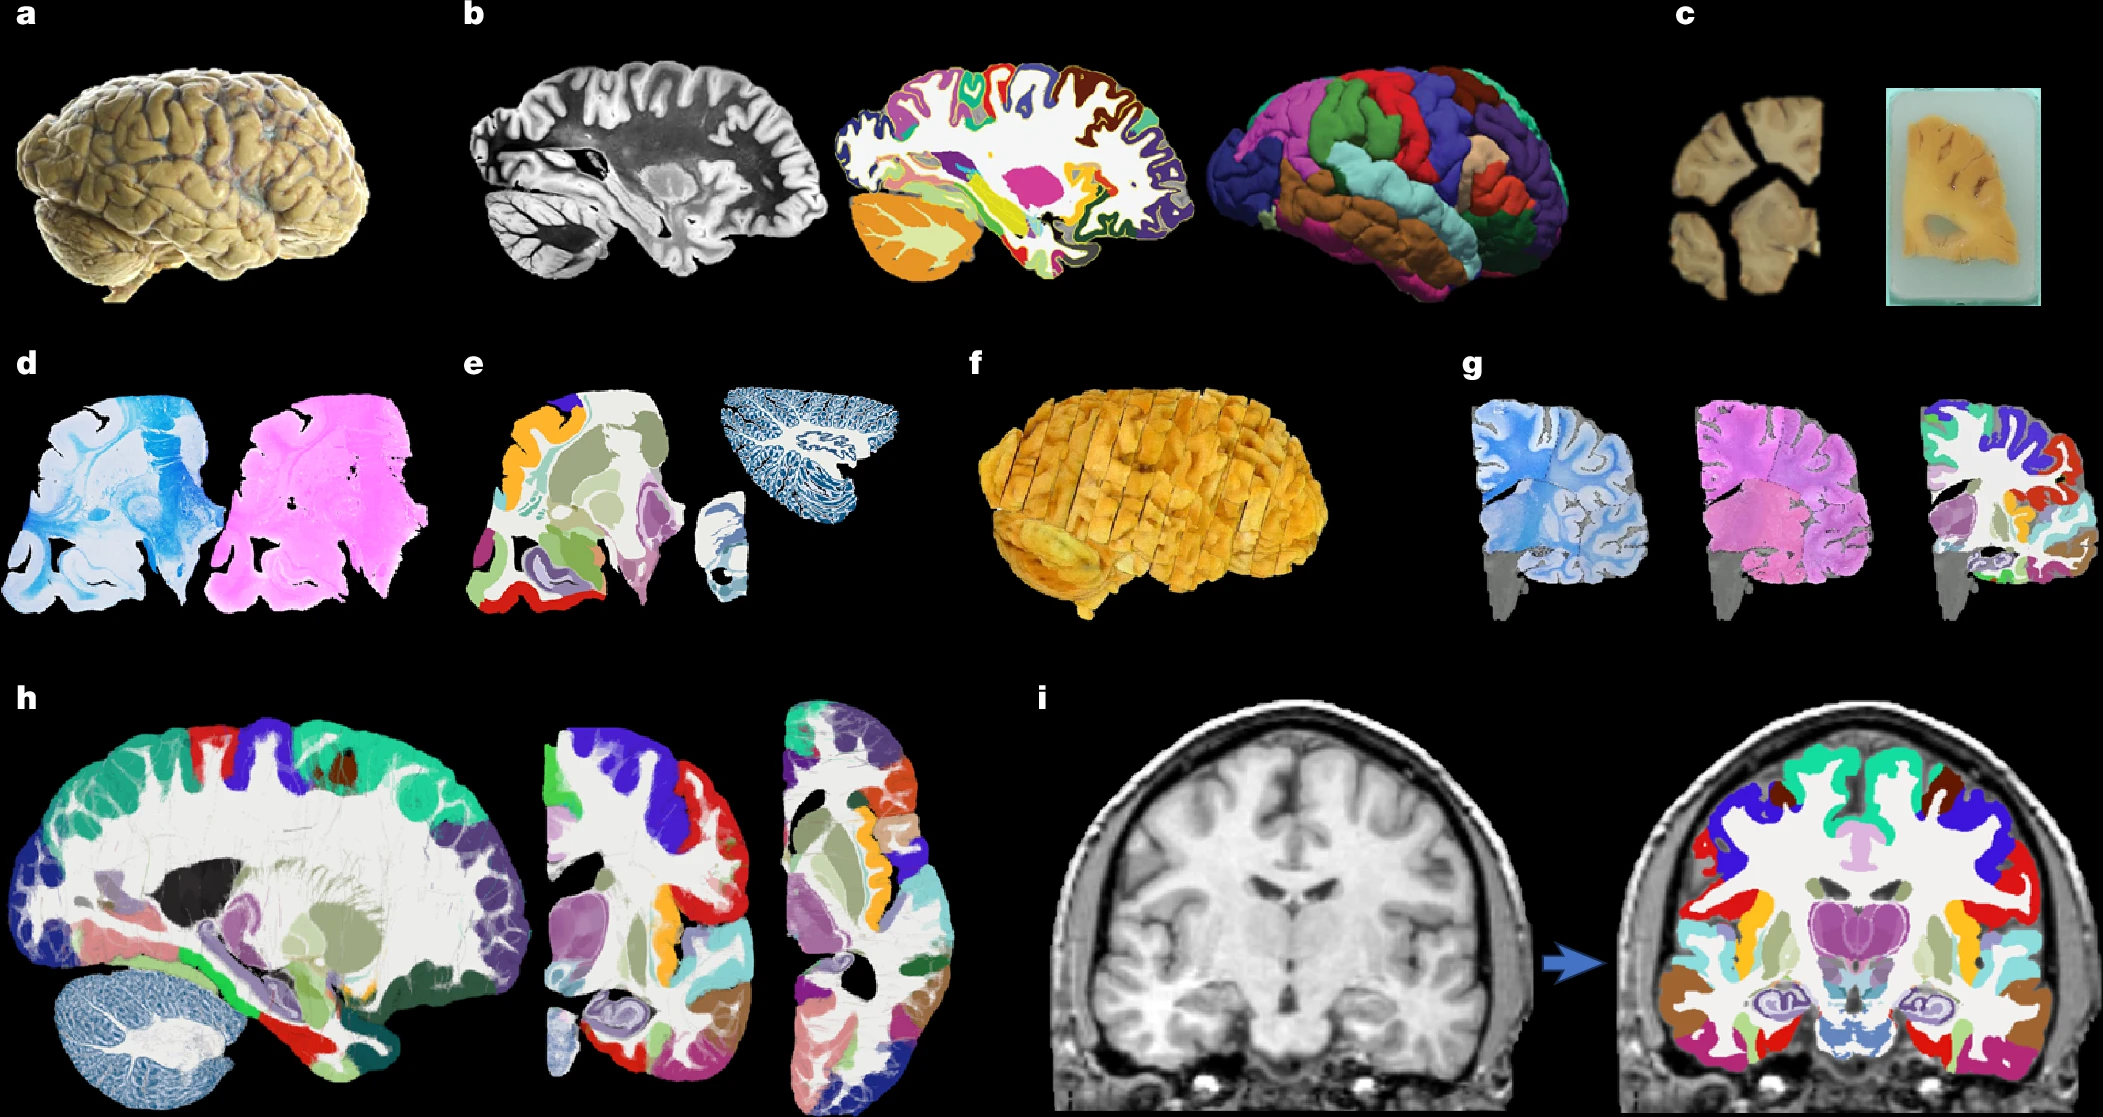

Un estudio desarrolla el mapa más completo y detallado del cerebro humano hecho hasta ahora, gracias a la inteligencia artificial. El atlas, llamado NextBrain, se ha publicado en la revista Nature y representa un paso adelante clave para entender y diagnosticar enfermedades neurológicas como el Alzheimer. El investigador Adrià Casamitjana, del grupo de investigación VICOROB de la Universitat de Girona (UdG) es el primer autor, fruto de su estancia postdoctoral en el University College London (UCL), donde ha colaborado con expertos internacionales en neuroimagen e ingeniería biomédica.

El atlas NextBrain, que ha sido desarrollado gracias a la ayuda de técnicas avanzadas de inteligencia artificial, es capaz de visualizar el cerebro humano in vivo a partir de resonancias magnéticas (RM) con una precisión sin precedentes.

El atlas NextBrain es el resultado de seis años de trabajo con muestras de tejido cerebral post mortem de cinco cerebros humanos. Cada cerebro fue diseccionado en más de 10.000 secciones microscópicas, teñidas, fotografiadas y reconstruidas digitalmente para crear un modelo 3D. La inteligencia artificial permitió alinear estas imágenes con escáneres MRI previos, corrigiendo distorsiones y otros artefactos provenientes de la disección, asegurando así una reconstrucción precisa.

A partir de este proceso, los investigadores identificaron y etiquetaron 333 regiones cerebrales, un trabajo que sin IA habría requerido décadas. El resultado es un atlas probabilístico representativo de la estructura cerebral adulta, aplicable tanto a cerebros vivos como a muestras post mortem.